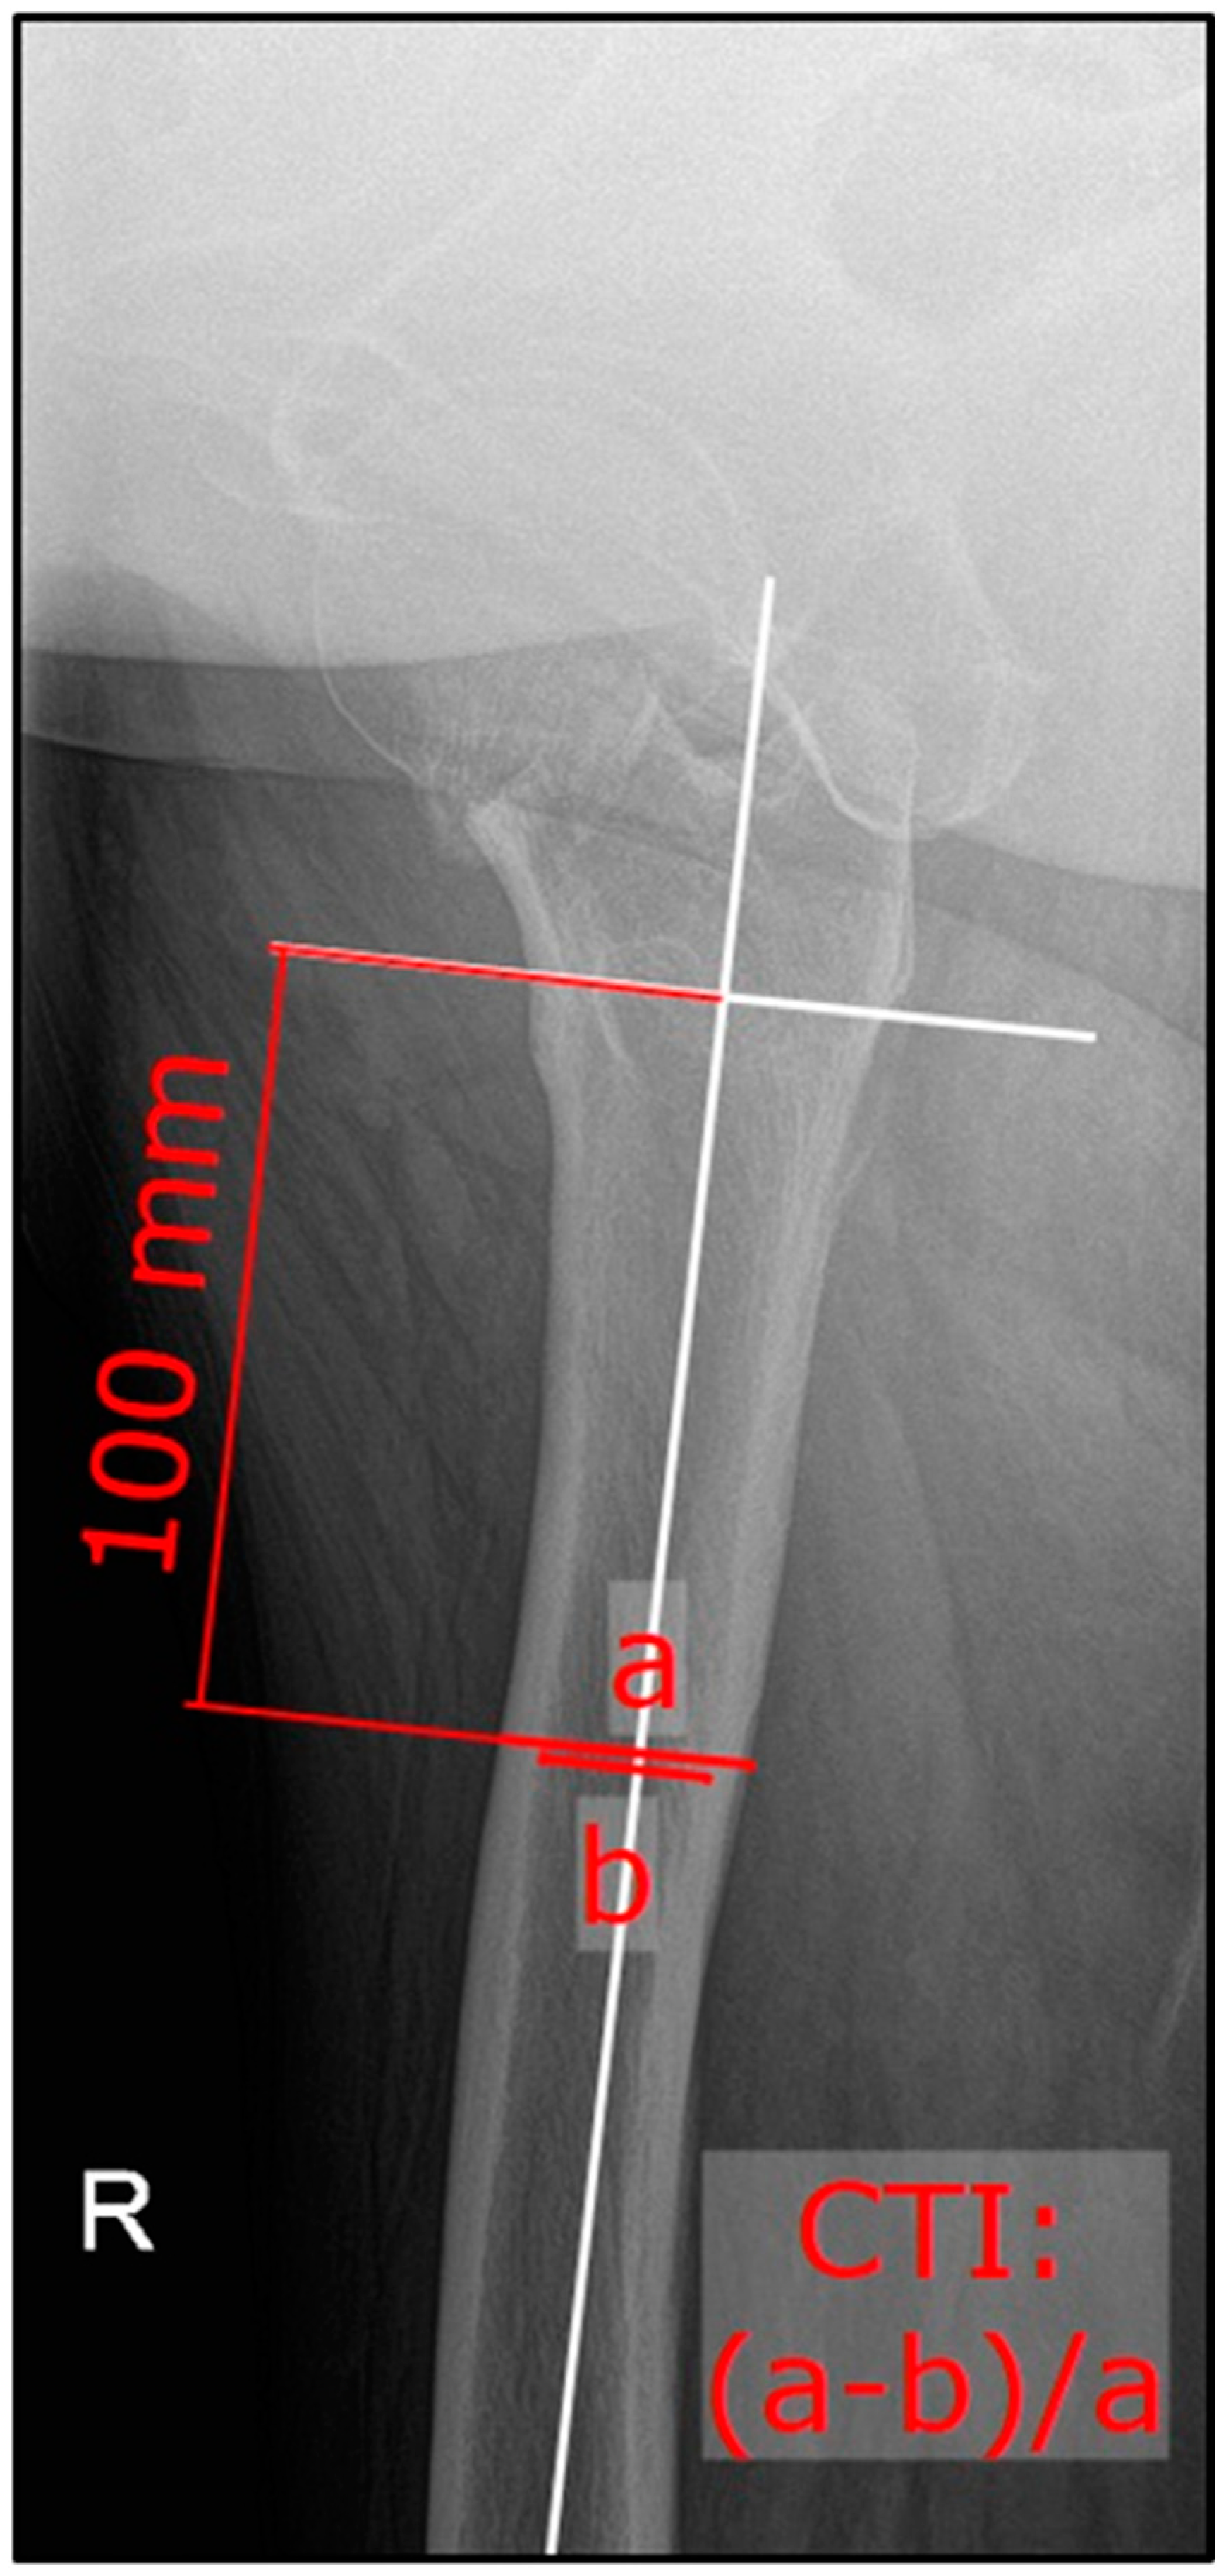

2. Materials and Methods

3.3. Comparison of CTI and CCR within the Sub-Groups